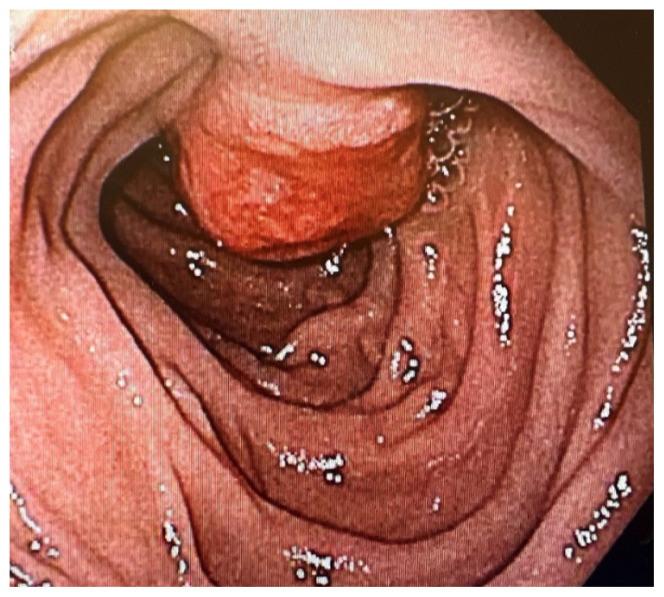

Massive Upper Gastrointestinal Bleeding Secondary to a Large Pedunculated Brunner Gland Hamartoma in the Duodenum.

十二指肠大带蒂布伦纳腺错构瘤继发的大量上消化道出血。